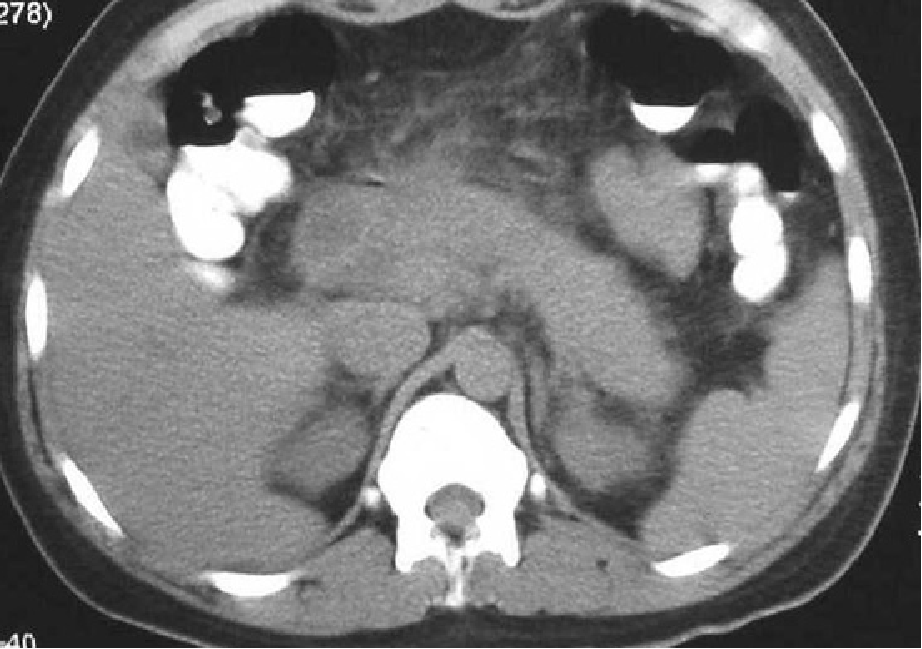

A:38岁,女患,急性间质水肿性胰腺炎,白箭头所示左肾周前间隙急性胰周液体积聚。胰腺完全强化,增大,但由于水肿导致强化不均匀。急性胰周液体积聚呈液体密度,无囊壁包裹。B:几周后,随访CT发现急性胰周液体积聚完全吸收,残留极少胰周脂肪毛糙影。

(2)CT对胰腺炎的严重程度有较大价值

CT-胰腺实质密度增高或降低,体积增大,胰周浸润。

增强CT-清楚显示胰腺坏死区域、范围